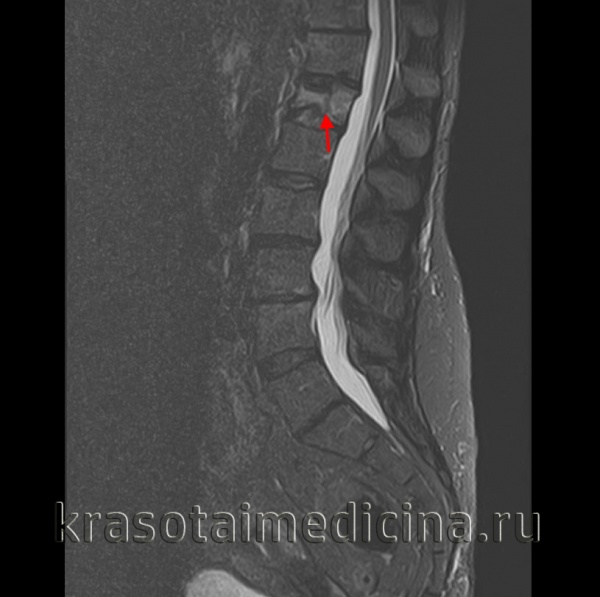

(Слева) КТ, сагиттальный срез: тяжелый взрывной перелом тела L5 позвонка со смещением крупного фрагментав спинномозговой канал. Несмотря на выраженный стеноз спинномозгового канала неврологического дефицита у данного пациента не было.

(Справа) КТ, сагиттальный срез: взрывные переломы Т5 и Т3 позвонков. Поскольку грудная клетка стабилизирована ребрами и грудиной, наличие здесь взрывных переломов свидетельствует о значительной силе травмирующего воздействия.